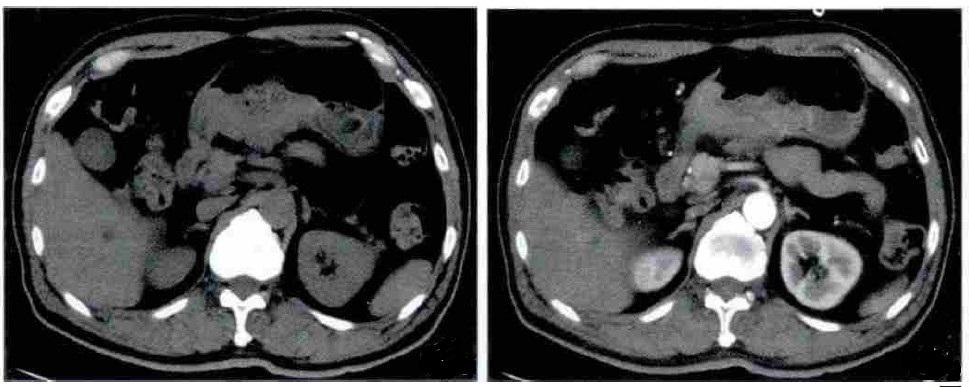

胃间质瘤根据病变发生部位与胃壁的关系可分为黏膜下型、肌间型、浆膜下型及胃外型,黏膜下型胃间质瘤好发于胃体及胃底,多表现为黏膜下软组织肿块,向胃腔内生长,表面有小的脐样切迹或形成较大的液平,增强后动脉期轻度较均匀强化,门静脉期持续性较均匀强化。

胃间质瘤主要影像学特点

发病位置:以胃体部大弯侧最多,其次胃窦部;向腔内、腔外或同时向腔内外突出生长,以腔外生长多见;

恶性者:直径多>5cm,形态欠规则,可呈分叶状,密度不均匀,可有坏死、囊变、陈旧性出血所致低密度灶;

增强呈中等或明显强化,囊实性者周边实性成分强化明显,肿瘤表面可见强化明显、完整的黏膜面,可见索条状细小血管;

强化峰值很少达到100HU以上。